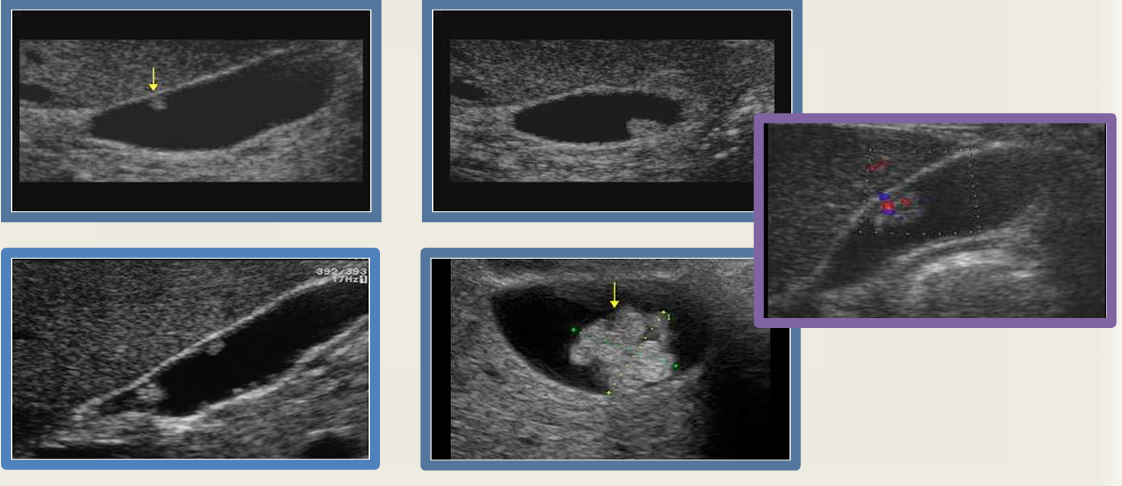

emphysematous cholecystitis

GB perforation

GB carcinoma

milk of calcium

GB polyps

chronic cholecystitis

Mirizzi syndrome